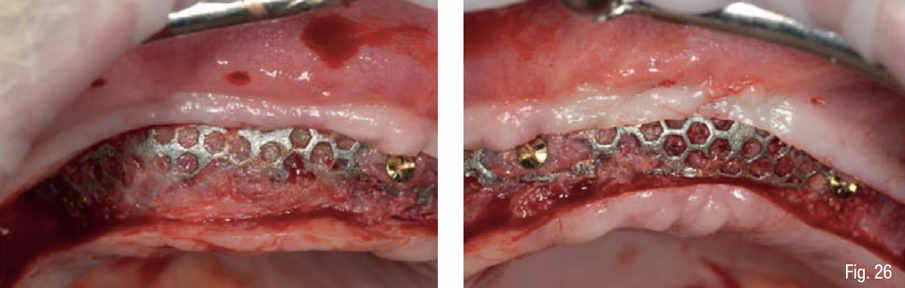

Durante la fase di chirurgia implantare, è stata inizialmente fissata la dima chirurgica sfruttando l’appoggio dento-mucoso; successivamente, è stata eseguita un’incisione lineare crestale e si è proceduto al sollevamento di un lembo vestibolare a tutto spessore e alla rimozione delle mini-viti e della griglia, che essendo osteointegrata in diversi punti è stata rimossa in diversi frammenti. La percentuale di rigenerazione, ovvero il rapporto tra il volume osseo rigenerato e il volume osseo pianificato, è stato calcolato essere del 96% (Figg. 25-29). La dima chirurgica è stata riposizionata e fissata nuovamente mediante i pin di fissaggio precedente preparati, non avendo più il supporto mucoso. Usando una tecnica di sotto-preparazione, sono stati realizzati i siti implantari e sono poi stati inseriti i 6 impianti programmati: 4 impianti dritti con dimensione 10 x 3.7 mm e 2 impianti angolati a 25° con dimensione 12 x 3.7 mm, al fine di evitare il seno mascellare (BTK implant Isy+, Biotec Srl, Dueville, Vicenza, Italy) (Fig. 30).